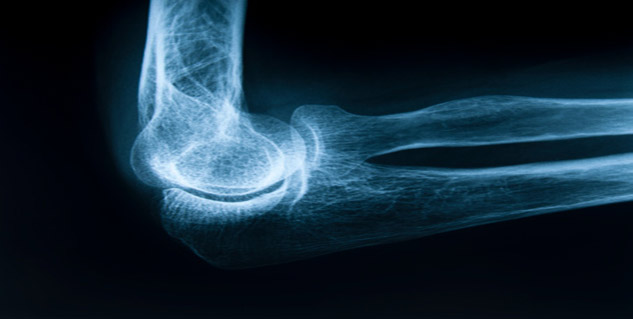

वैज्ञानिकों ने एक ऐसे तंत्र की पहचान की है जो बताता है कि बुजुर्गो की हड्डियों में कमजोरी क्यों आ जाती है. साथ ही शोधकर्ताओं ने ऐसा तरीका खोज निकाला है, जिसके जरिए भविष्य में बढ़ती उम्र के साथ हड्डियां कमजोर होने के इलाज में काम आ सकता है. शोधकर्ताओं ने पाया कि ऑस्टियोपेरोसिस यानी हड्डी के पतलेपन और घनत्व में कमी के कारण हड्डी टूटने का खतरा बढ़ जाता है. यह बुजुर्गो की एक प्रमुख स्वास्थ्य समस्या है. अक्सर ये हालात अस्थि मज्जा में वसा कोशिकाओं की वृद्धि के साथ पैदा होते हैं.

बर्मिघम के अलबामा युनिवर्सिटी के प्रोफेसर यू-पिंग ली के नेतृत्व में हुए एक अध्ययन में सामने आया है कि सीबीएफ-बीटा नामक एक प्रोटीन हड्डियों के बनने में मददगार कोशिकाओं को शरीर में बनाए रखने में महत्वपूर्ण भूमिका निभाता है.

चूहों पर किए गए एक परीक्षण में पाया गया कि युवा चूहों की तुलना में वृद्ध चूहों की अस्थि मज्जा कोशिकाओं में सीबीएफ-बीटा का स्तर नाटकीय रूप से कम पाया गया. इस निष्कर्ष से पता चलता है कि इस तंत्र में खराबी आने पर, कोशिकाएं हड्डियों को बनाने में मदद करना बंद कर देती हैं और वसा कोशिकाओं को बनाने में मदद करती हैं.

ली ने कहा, सीबीएफ-बीटा नाम के प्रोटीन को बनाए रखना मानव आयु-संबंधित ऑस्टियोपेरोसिस को रोकने में मदद कर सकता है. शोध का परिणाम नेशनल एकेडमी ऑफ साइंसेज की पत्रिका 'प्रोसीडिंग्स' में प्रकाशित किया गया है. शोधकर्ताओं का कहना है कि इस तंत्र की जानकारी होने से कम से कम साइड इफेक्ट के साथ मानव अस्थि मज्जा का इलाज किया जा सकता है.